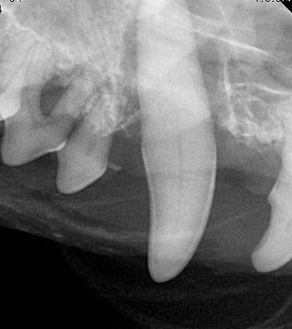

BEFORE

AFTER